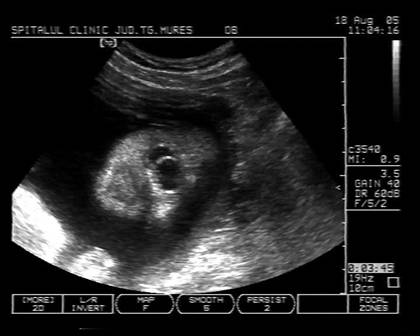

Fig. nr.250. Ciclopie diagnosticata la 17 sapt.